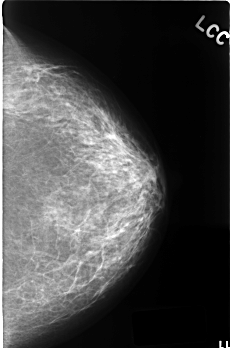

C_0384_1.LEFT_CC

LEFT_CC LINES 4520 PIXELS_PER_LINE 2984 BITS_PER_PIXEL 12 RESOLUTION 50 NON_OVERLAY